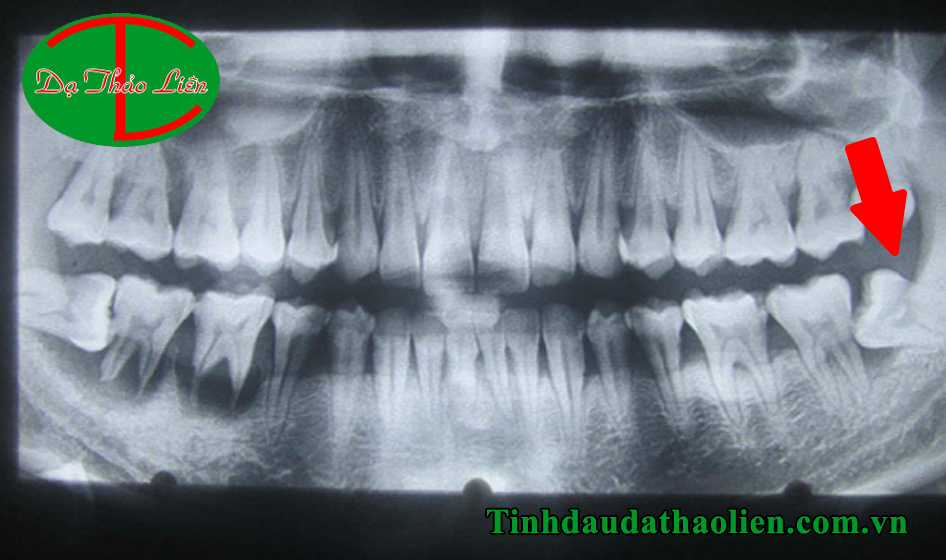

Đau răng do mọc răng khôn, răng mọc ngầm

Răng khôn hay răng số 8 thường mọc khi bạn bắt đầu ở độ tuổi trưởng thành. Răng khôn mọc thường hay mọc ngầm bên trong nướu và thường mọc lệch đâm vào nướu và các răng bên cạnh gây ra các biến chứng sưng đau vô cùng khó chịu. Nhiều khi răng số 8 mọc trong thời gian rất lâu nên gây ra hiện tượng nhiễm trùng nướu răng gây đau nhức.